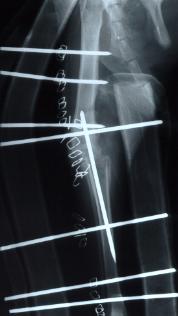

- Verplaatsen van de beenkam op het onderbeen, hierdoor wordt de knieschijf meer naar buiten getrokken waardoor hij gemakkelijker in de sleuf van de femur blijft.

-

- pijltje wijst de verplaatste beenkam aan